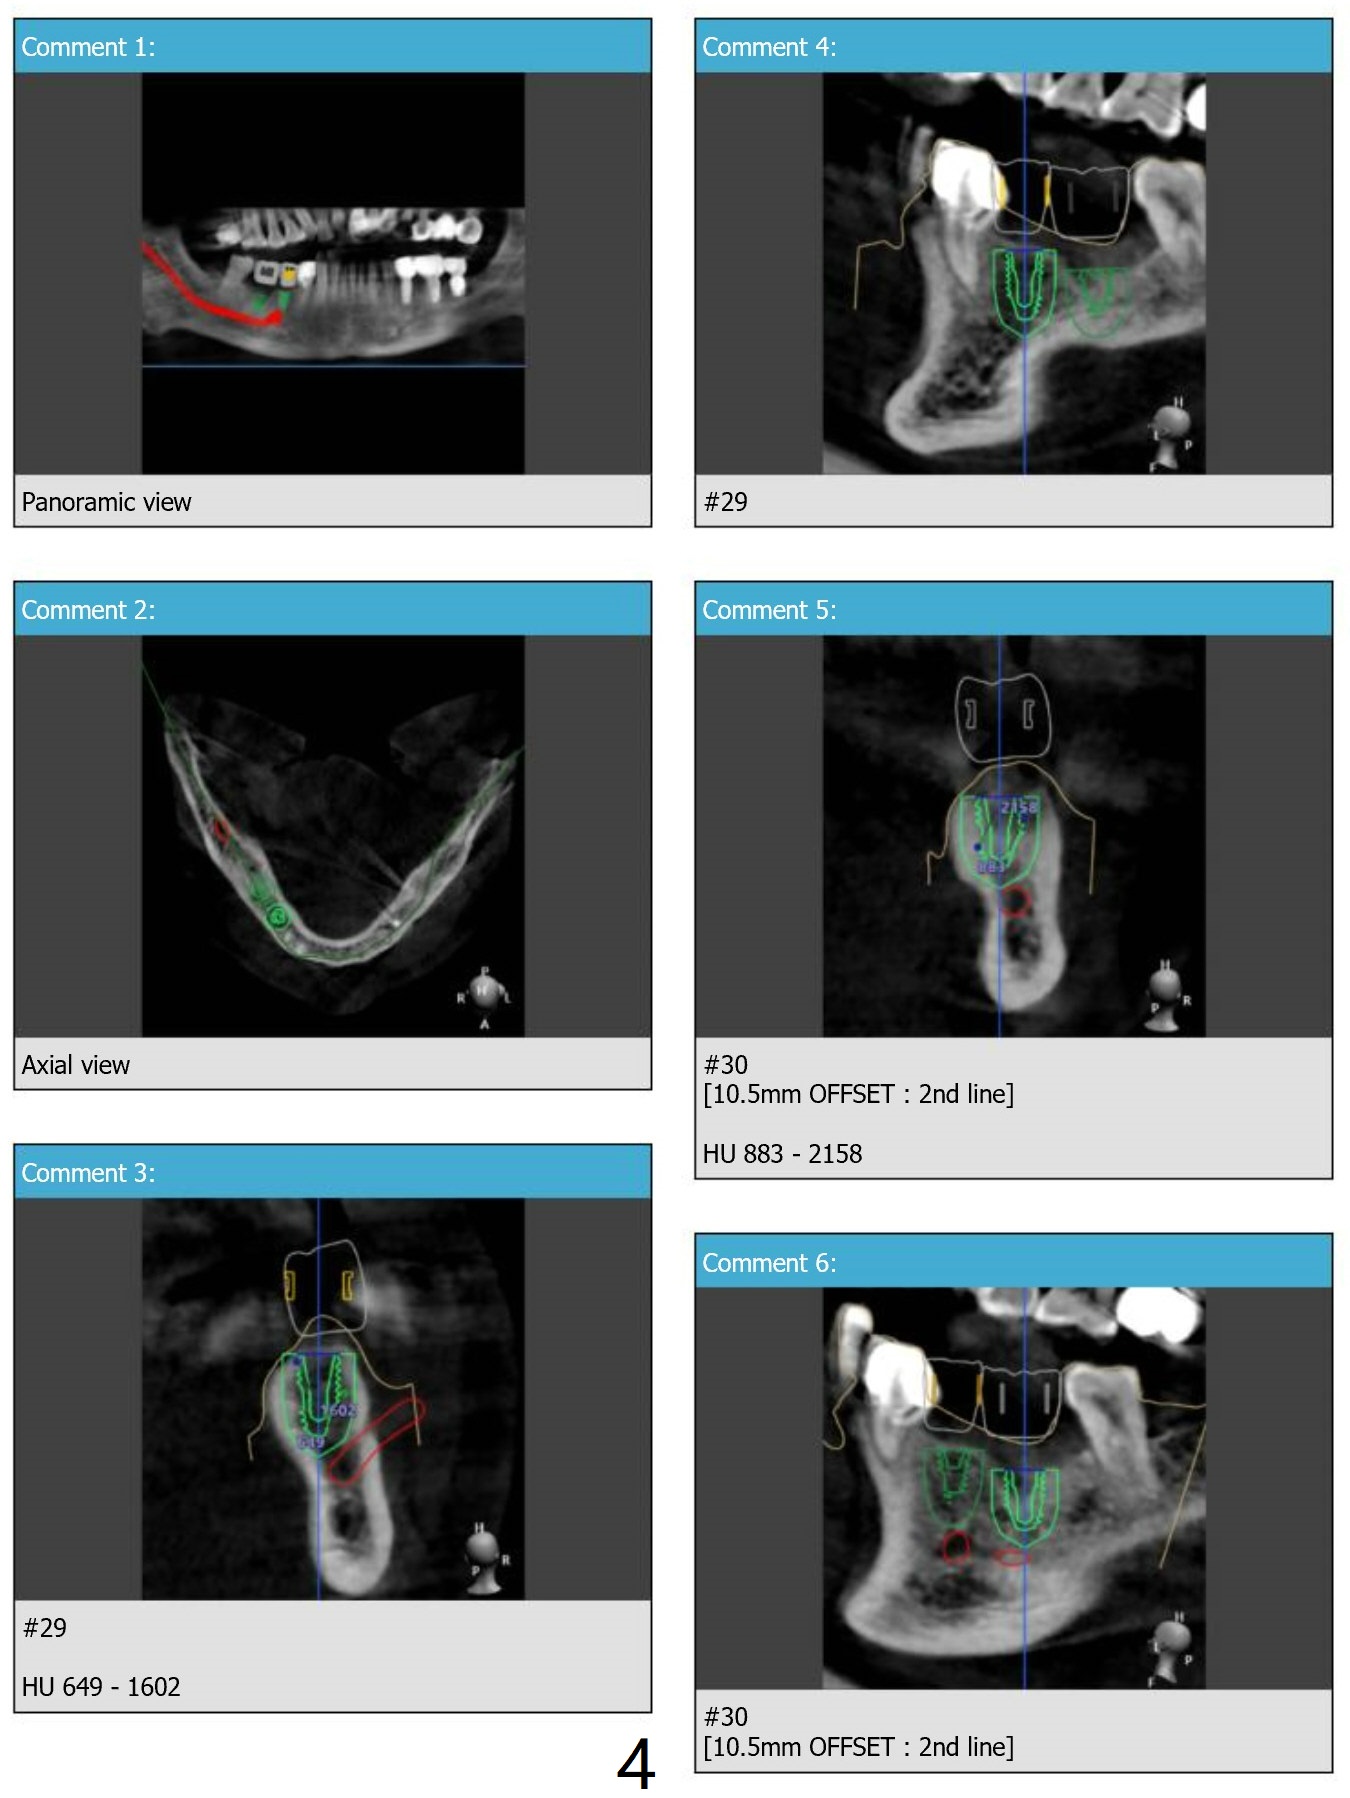

Hard Bone: Prevent Burning

Return to Lower Arch  Molar Premolar  Immediate Implant, Trajectory